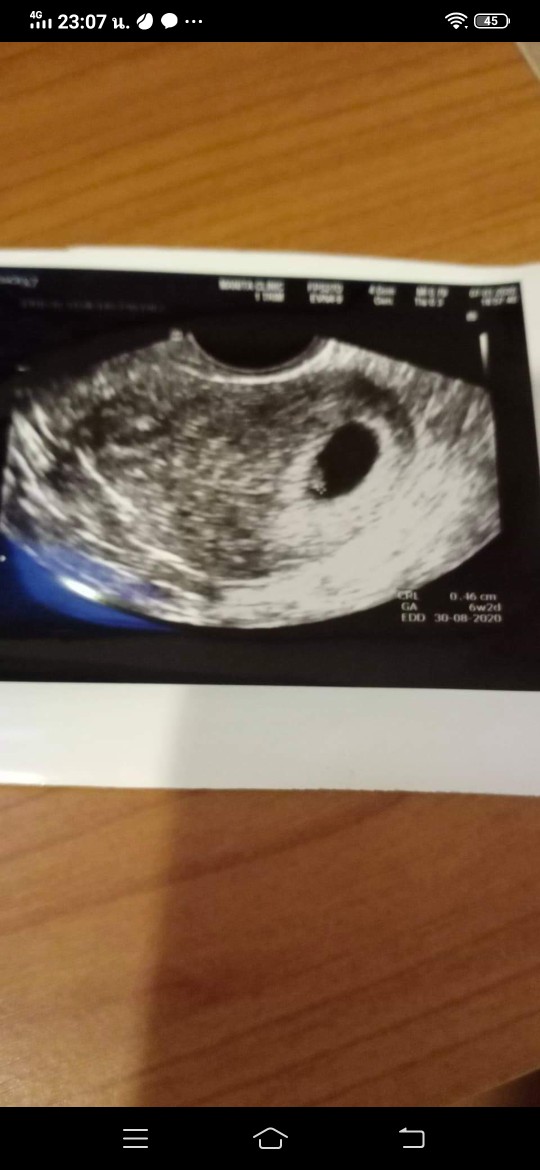

ถุงตั้งครรภ์ 6 สัปดาห์ แบบนี้ปกติไหมคะ กังวลมากเลยค่ะ

อัลตร้าซาวด์แล้วเจอแต่ถุงตั้งครรภ์แบบนี้ปกติมั้ยคะ

อันนี้ของแม่ตอน 6 W เจอแค่ถุงไม่เจอหัวใจ เจออีกทีตอน8W ตอนนี้โตละ 12W แล้วค่ะ

แล้วแบบนี้6วีคปกติมั้ยค่ะแม่ๆ แต่ยังไม่ได้ยินเสียงหัวใจด้วยค่ะ

6สัปดาห์2วันค่ะ ได้ยินเสียงหัวใจเบาๆ หมอบอกน้องยังเล็กมาก😊😊